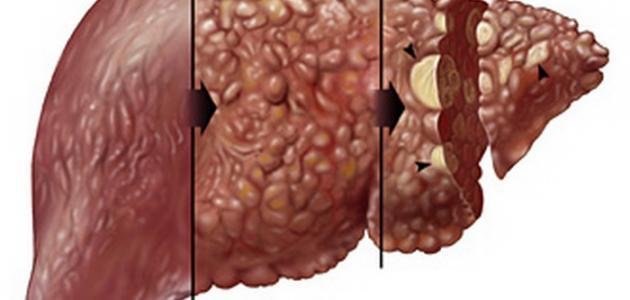

أعراض تليف الكبد وعلاجه

أعراض تليف الكبد وعلاجه

| 1 | تليف الكبد هو عملية تلين وتليث الأنسجة الكبدية. |